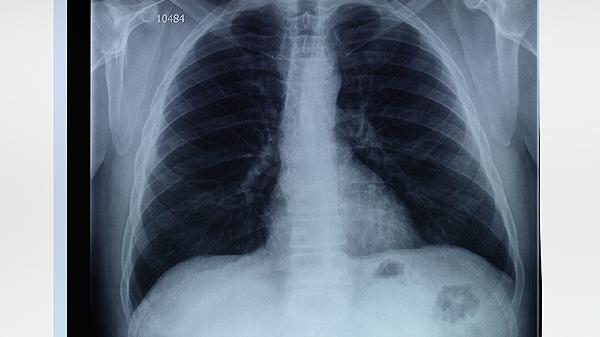

右肺上叶肺大泡是否严重需结合具体病情判断,多数情况下体积较小的肺大泡无明显症状,但体积较大或合并感染时可能引发气胸等并发症。肺大泡是肺泡结构破坏形成的异常气囊,常见于慢性阻塞性肺疾病、长期吸烟或肺部感染患者。

当肺大泡直径超过5厘米或占据单侧胸腔三分之一以上时,可能出现持续胸痛、突发呼吸困难等症状,此时易发生自发性气胸。若合并感染还会伴随发热、咳嗽咳痰,需通过胸腔闭式引流术排出气体,必要时行肺大泡切除术。先天性α-1抗胰蛋白酶缺乏症患者更易进展为巨型肺大泡。